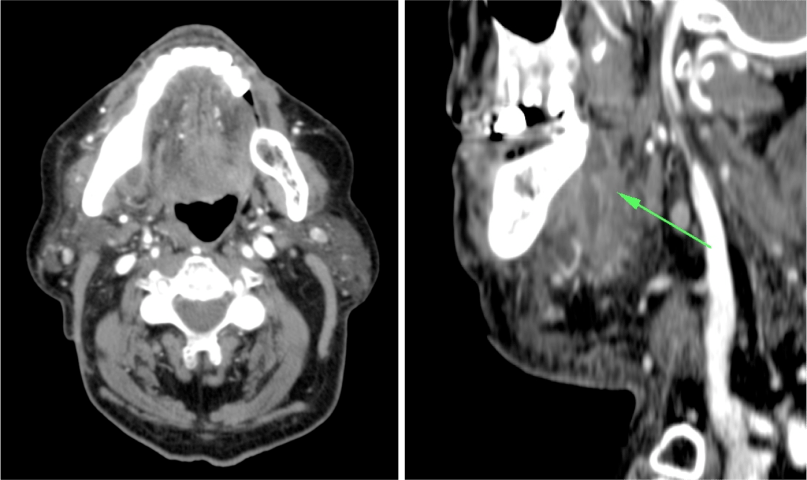

ESPACIO SUBLINGUAL Y SUBMANDIBULAR. ANGINA DE LUDWING:

Espacio sublingual:

Se sitúa inferior a la porción móvil de la lengua pero superior y medial al músculo milohioideo = Colecciones en esta localización son las denominadas sublinguales (las reconstrucciones coronales y sagitales son fundamentales). Contiene además a la glándula sublingual y una pequeña porción del aspecto superior de la glándula submandibular. Igual que en el espacio submandibular, las infecciones se manifiestan clínicamente por tumefacción, dolor, rubicundez y aumento de temperatura cervical. La mayoría son de origen dentario:

Espacio submandibular:

El espacio submandibular se sitúa inferior y lateral al músculo milohioideo. Es posterior al borde libre del milohioideo y comunica con el espacio sublingual (ver foto arriba). Contiene además la glándula submandibular, ganglios y a veces pueden localizarse quistes branquiales.

Angina de Ludwing:

No es un absceso, es una celulitis multiespacial ya que afecta al suelo de la boca y los espacios sublingual y submandibular. Se manifiesta clínicamente por dolor, hinchazón, disfagia, fiebre y elevación de la lengua, puede asociar crepitación si se deben a microrganismos anaerobios. En la TC con contraste se observa:

- Realce y edema difuso de los componentes del suelo de la boca.

- Debe determinarse si existe colección susceptible de drenaje, permeabilidad de la vía aérea y presencia de aire secundario al crecimiento de microorganismos anaerobios.

- La infección causa elevación y desplazamiento de la lengua que puede cerrar la vía aérea (debe tenerse en cuenta a la hora de manejar estos pacientes antes de realizar la prueba).